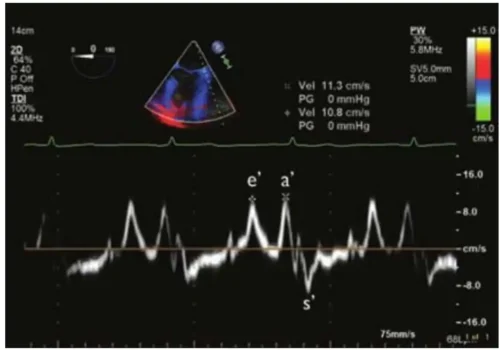

💡اجزای تشکیلدهندهٔ طیف داپلر

طیف داپلر، هستهٔ اصلی داپلر طیفی است و تمام اطلاعات کمی و کیفی جریان خون از طریق شکل، ارتفاع، پهنا و الگوی این طیفها استخراج میشود. شناخت اجزای تشکیلدهندهٔ طیف داپلر برای تفسیر صحیح یافتهها ضروری است، زیرا هر بخش از این نمودار بازتابی از رفتار واقعی جریان خون در قلب و عروق است. این فصل بهصورت مرحلهبهمرحله اجزای کلیدی طیف داپلر را معرفی و نقش هرکدام را در ارزیابی بالینی توضیح میدهد.

طیف داپلر بر روی یک نمودار دو محوره نمایش داده میشود. محور افقی نشاندهندهٔ زمان است و محور عمودی سرعت جریان خون را نشان میدهد. این ساختار دو بعدی به پزشک اجازه میدهد تغییرات سرعت را در طول چرخهٔ قلبی دنبال کند و الگوهای سیستولیک و دیاستولیک را بهصورت دقیق تحلیل نماید. این ویژگی داپلر طیفی را از سایر روشهای تصویربرداری متمایز میکند.

یکی از مهمترین اجزای طیف داپلر، پوشش موج یا Envelope است. این پوشش، مرز بیرونی طیف را تشکیل میدهد و نشاندهندهٔ بیشترین سرعت جریان در هر لحظه است. پزشک معمولاً برای محاسبهٔ سرعتهای حداکثر، گرادیان فشار یا شدت تنگیها از همین پوشش موج استفاده میکند. کیفیت و وضوح Envelope نقش مهمی در دقت اندازهگیری دارد.

در کنار Envelope، بخش دیگری از طیف به نام Spectral Broadening یا پهنشدگی طیف وجود دارد. این پهنشدگی زمانی رخ میدهد که سرعتهای مختلفی در یک نقطهٔ نمونهبرداری وجود داشته باشد. جریانهای منظم یا Laminar Flow طیفی باریک و یکنواخت ایجاد میکنند، در حالیکه جریانهای آشفته یا Turbulent Flow طیفی پهن و نامنظم دارند. مشاهدهٔ این پهنشدگی یکی از ابزارهای مهم برای تشخیص تنگیها، نشتها و جریانهای غیرطبیعی است.

یکی دیگر از اجزای مهم طیف داپلر، Baseline یا خط پایه است. این خط محور صفر سرعت را نشان میدهد و تعیین میکند که جریان به سمت پروب قرار دارد یا از آن دور میشود. جریانهای بالای خط پایه معمولاً به سمت پروب هستند و جریانهای زیر خط پایه از پروب دور میشوند. تنظیم صحیح Baseline برای جلوگیری از آلیاسینگ و نمایش واضح موجها اهمیت زیادی دارد.

در طیف داپلر، جهت جریان نیز نقش مهمی دارد. در بسیاری از ساختارهای قلبی، جریان ورودی و خروجی در جهتهای متفاوتی نسبت به پروب قرار میگیرند. به همین دلیل، پزشک باید بداند که موجهای مثبت و منفی در هر نما چه معنایی دارند. این موضوع بهویژه در ارزیابی جریانهای میترال، تریکوسپید و خروجی بطنها اهمیت دارد.

یکی از ویژگیهای مهم طیف داپلر، امکان مشاهدهٔ الگوهای سیستولیک و دیاستولیک است. موجهای سیستولیک معمولاً باریکتر و با سرعت بالاتر هستند، در حالیکه موجهای دیاستولیک بسته به نوع جریان، شکلهای متفاوتی دارند. این الگوها در تشخیص اختلالات دیاستولیک، تنگیها و نارساییها نقش کلیدی دارند.